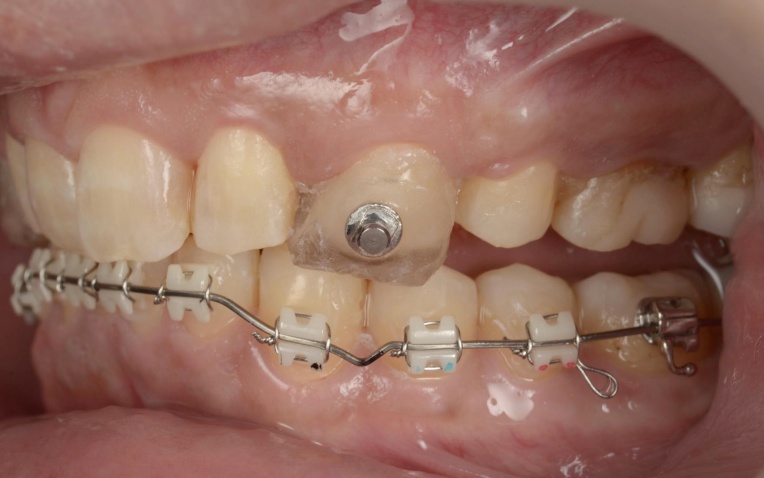

まずはバイト挙上を行います。上顎には、下顎の位置を安定させるための「スプリント」を使用し、下顎奥歯には噛み合わせを調整するための仮歯を装着しました。

この状態で下顎にのみワイヤーを装着し、安定した下顎の位置をキープしながらワイヤー矯正治療へ移行します。

そのため、上顎前歯には上顎のスプリントを必要な部分だけカットして歯に直接接着し、噛み合わせの高さを維持するストッパーとして活用しました。

これにより、上顎の装置が矯正のガイド役となり、安定した下顎の位置を崩さずに精密なワイヤー矯正を行うことが可能です。

また、上顎には上下の噛み合わせの前後関係を整えるための補助装置「顎間ゴム」を使用し、噛み合わせを正しい位置関係へ導く「咬合(こうごう)誘導」を行っています。

治療中